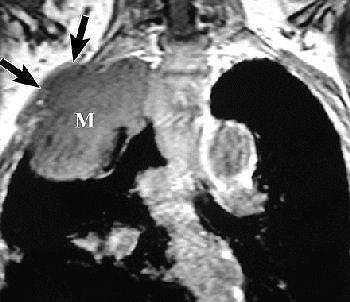

![]() |

R imaging evaluation of MPM in 63-year-old man. Coronal (top) and contrast-enhanced fat-saturated (below) T1-weighted MR images show a large, enhancing right apical mass with invasion of chest wall (black arrows, top). An enhancing right major fissure is also seen (white arrowheads, below). Figure 16, Wang ZJ, Reddy GP, et al, "Malignant Pleural Mesothelioma: Evaluation with CT, MR Imaging, and PET" (RadioGraphics 2004; 24: 105-119).

Investigators from the University of California, San Francisco came to similar conclusions, advocating MR imaging in patients with potentially resectable disease.

"The excellent contrast resolution of MR imaging can allow improved detection of tumor extension.... Loss of fat planes, extension into mediastinal fat, and tumoral encasement of more than 50% ... are some of the features that suggest tumor extension," wrote Dr. Zhen Wang and colleagues in an educational exhibit for RadioGraphics (January-February 2004, Vol. 24:1, pp. 105-119).

On T1-weighted MR images, malignant pleural mesothelioma (MPM) is typically isointense or hyperintense. On T2-weighted images, MPM is moderately hyperintense. In both cases, gadolinium enhances the disease, they added.

MRI may also prove superior for assessing the growth of MPM, either as an invasion of the diaphragm, invasion of the endothoracic fascia, or a single chest wall focus.